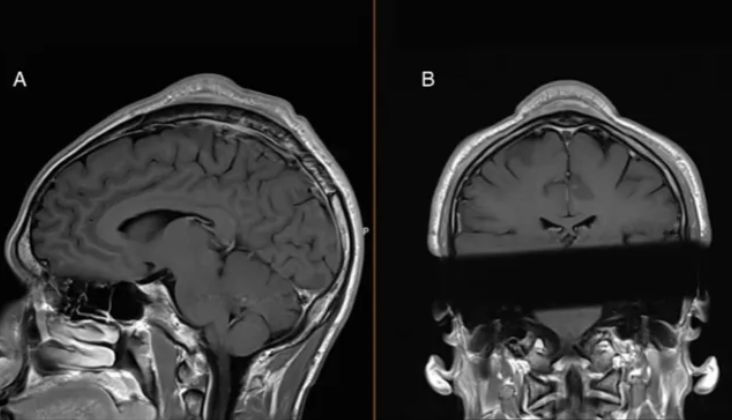

وأشار أطباء الرجل إلى أن "وجود الآفة وعدم الراحة المصاحب لها كانا مزعجين من الناحية الجمالية للمريض، لكن النتوء لم يمنع المريض من مواصلة أنشطة الدوران بالرأس". وعند فحص النتوء، لاحظ الأطباء أن الجلد الموجود فوقه يتحرك بسهولة، مما يشير إلى أن الكتلة كانت محصورة بين الجلد والجمجمة. وقد أكد فحص هيكلي لرأس الرجل أن هذه كانت الحالة، كما أظهر أن الجلد فوق النتوء والجمجمة أدناه أصبح أكثر سمكًا من الأنسجة المحيطة بهما.